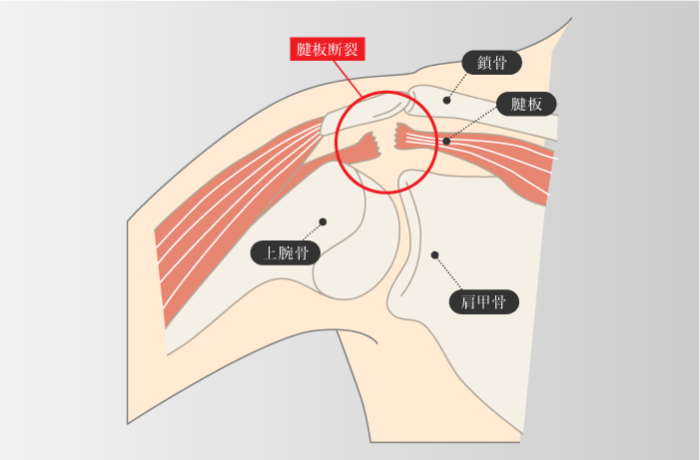

腱板損傷

-

関節の安定性をもたらす腱板に断裂などの損傷が生じた状態

※腱板を構成する筋は棘上筋、棘下筋、小円筋、肩甲下筋